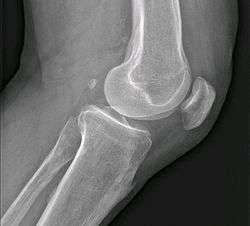

![]() Fabella is the small calcification appearing back of femoral condyles | |

The fabella (Latin for little bean) (or flabella) is a small sesamoid bone found in some mammals embedded in the tendon of the lateral head of the gastrocnemius muscle behind the lateral condyle of the femur. It is a variant of normal anatomy and present in humans in 10% to 30% of individuals.[1] Rarely, there are 2 or 3 of these bones (fabella bi- or tripartita). It can be mistaken for a loose body or osteophyte.